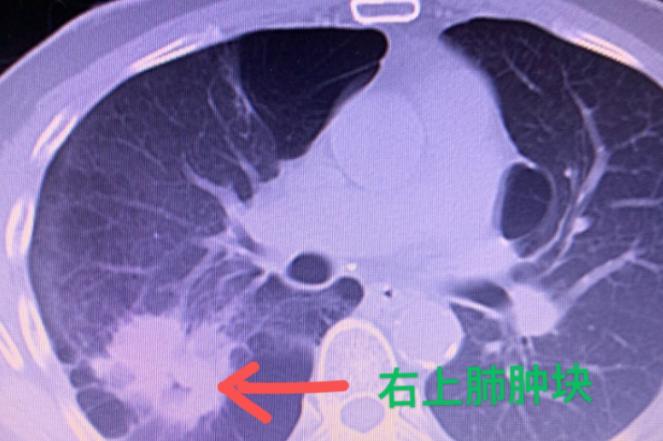

十年前他得过肺结核,虽然治好了,但一直咳嗽、胸闷。最近症状加重,做了CT才发现:肺里有个大肺大泡,还长了一个3×4厘米的肿瘤。

之前有医生怀疑是肺癌,但因为肺功能太差,肿瘤位置也不好,手术一直没人敢做。

手术很顺利,在胸腔镜下切除了右上肺的大泡和肿瘤,连同受侵犯的右下肺背段也一并拿掉了。术后他恢复得不错,自己都说呼吸顺畅多了。